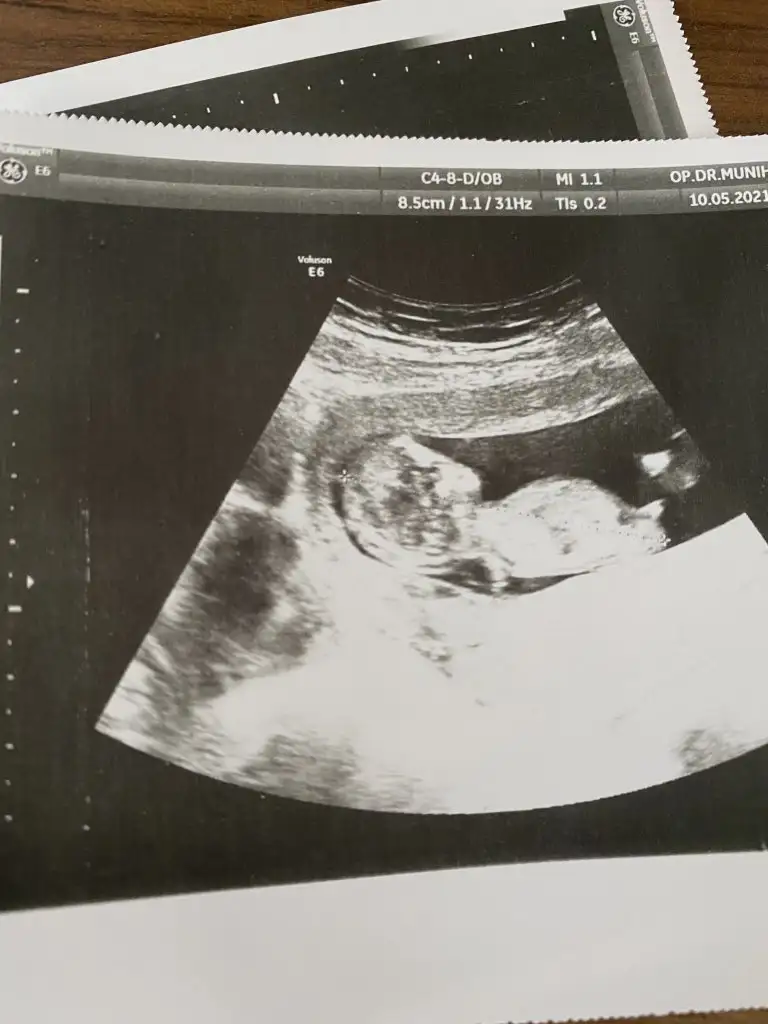

Nasıl anlıyorsunuz kizlarErkeeeekkkkk

Erkek benceBu da resmimiz tahmin alabilirim

Çok ediyor insan hayırlı evlad olsunSaglıkla dogsunlar inşallah canımcinsiyet fark etmiyor ama insan artık merkta ediyor dimi :)